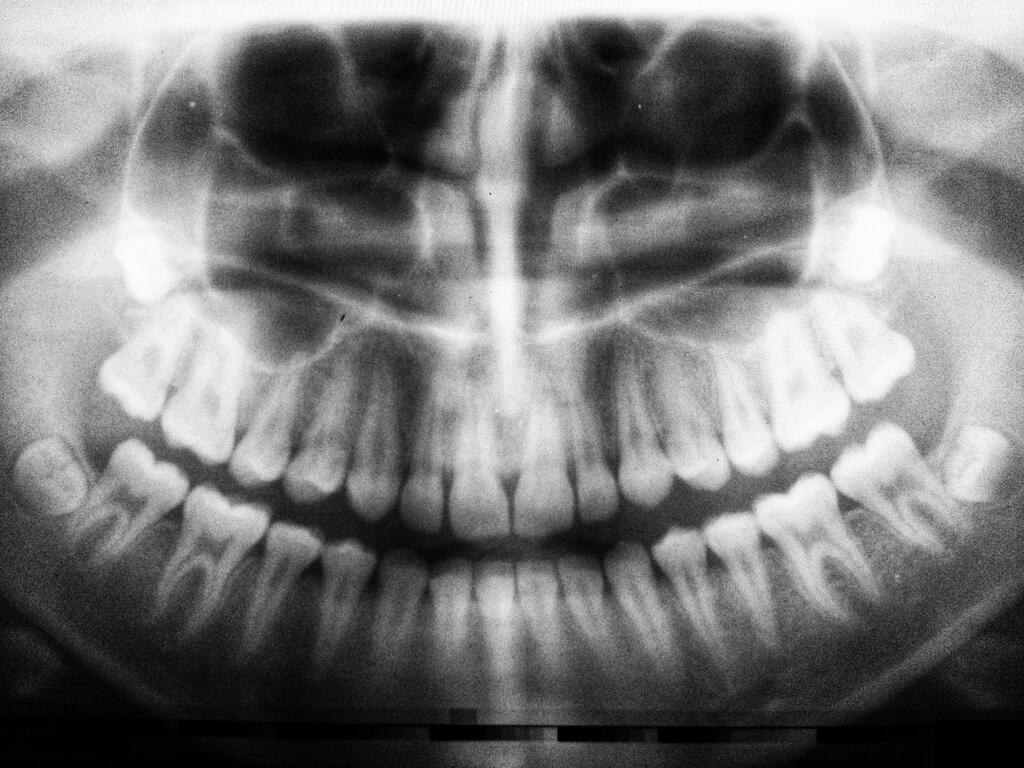

Синус-лифтинг является распространенной процедурой в стоматологии. На практике это медицинская процедура, при которой кость имплантируется в область дна верхнечелюстной пазухи. Костный трансплантат выполняется путем открытия небольшого окна и введения искусственного костного материала в нёбо. Кроме того, такие процедуры поднимают челюстную кость, что позволяет устанавливать зубные импланты. Однако лечение сопряжено с определенными рисками, и поэтому стоит ознакомиться с новыми и лучшими альтернативами.

Чтобы понять важность базальной трансплантации, нужно знать структуру и особенности синуса. Синус, или гайморова пазуха - это парная придаточная пазуха носа, занимающая практически всё тело верхнечелюстной кости.

Синус-лифтинг процедуры предназначены для создания дополнительной кости в задней части верхней челюсти. Добавление кости к задним частям верхней челюсти требуется в любом случае, когда требуются зубные импланты, например, при дефиците зубов. В надлежащем состоянии зубные импланты могут быть вставлены даже без подъема пазухи. С другой стороны, в условиях недостаточного объема кости имплантация не может быть выполнена, и поэтому требуется открытый или закрытый синус-лифтинг.